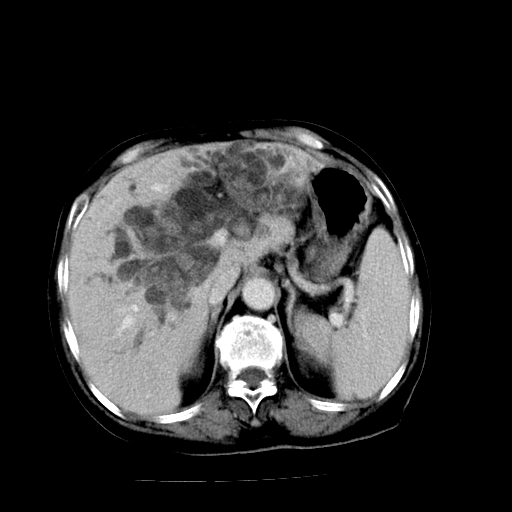

以下是引用随光逐影在2009-4-7 8:21:00的发言:[br]肝内外胆管多发性结石并肝内外胆管扩张;胆系感染。